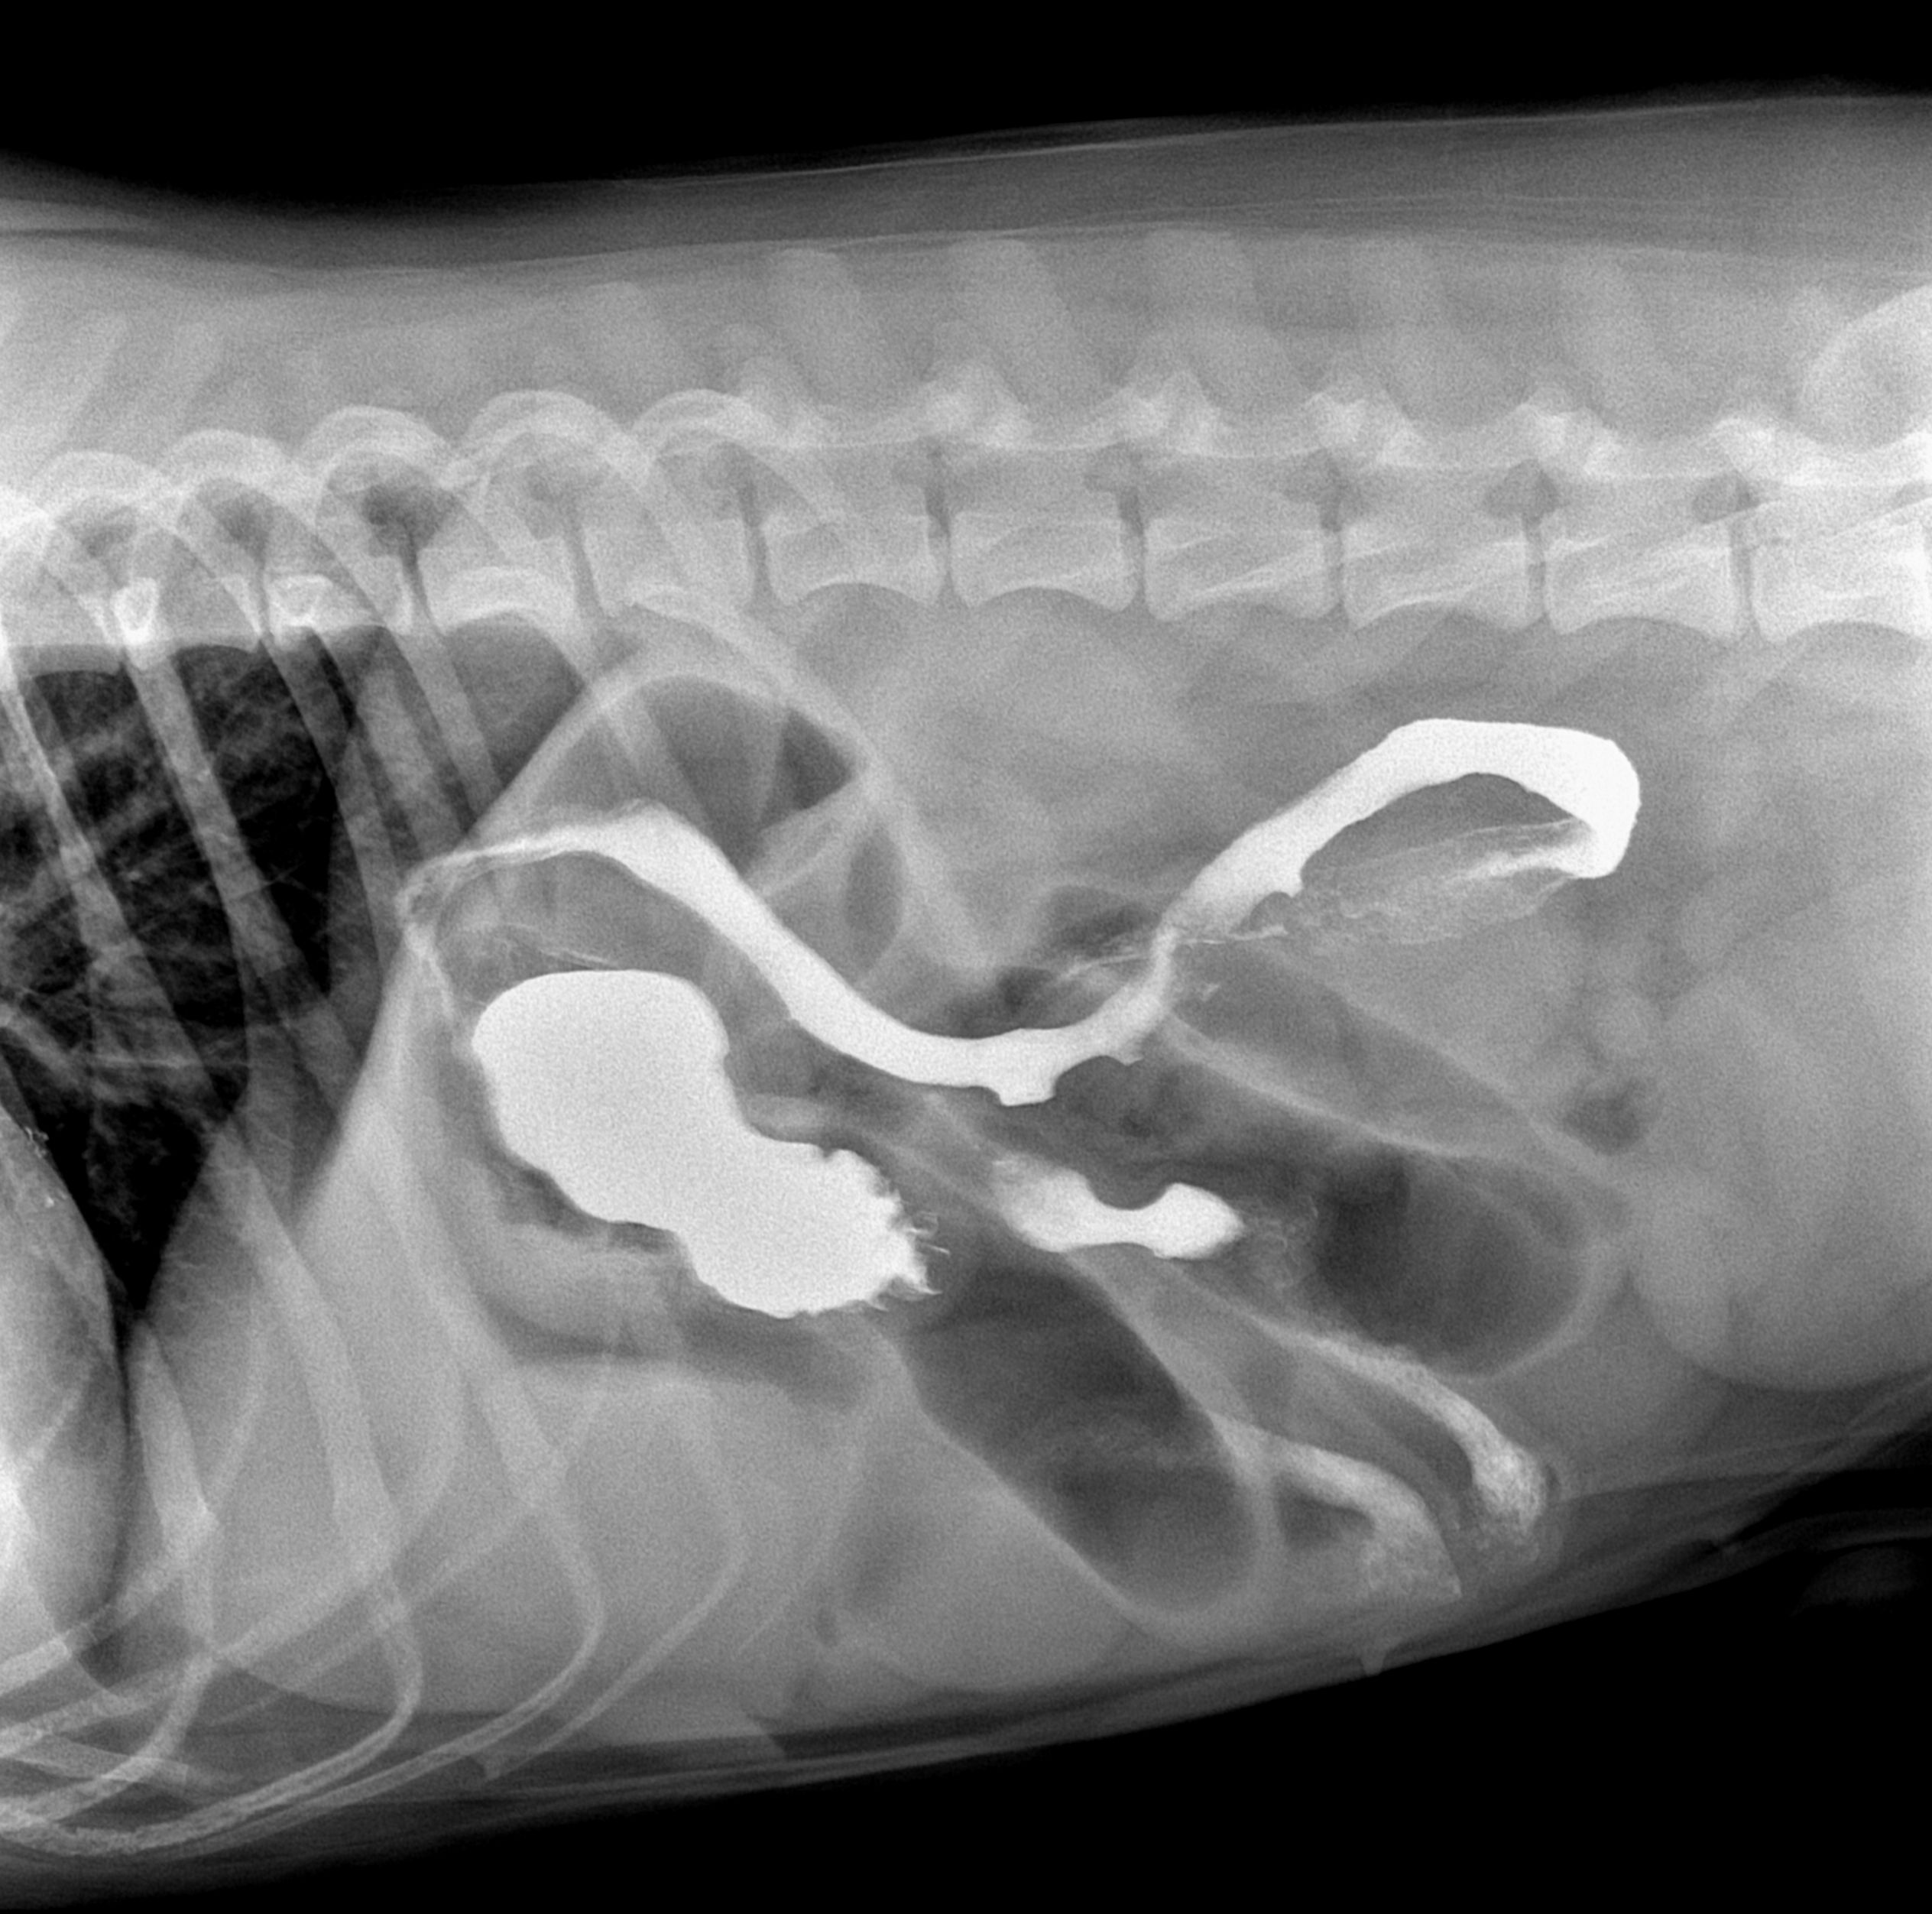

然后医生说给它做钡餐,晚上9点左右出结果了

2017年12月08日 08点12分 12

挺大一坨的不知道是什么东西,医生建议给它动手术,我犹豫了一下,第二天赶紧又去医院,它精神挺不错的,但是就是吐不出来, 没办法只能手术了